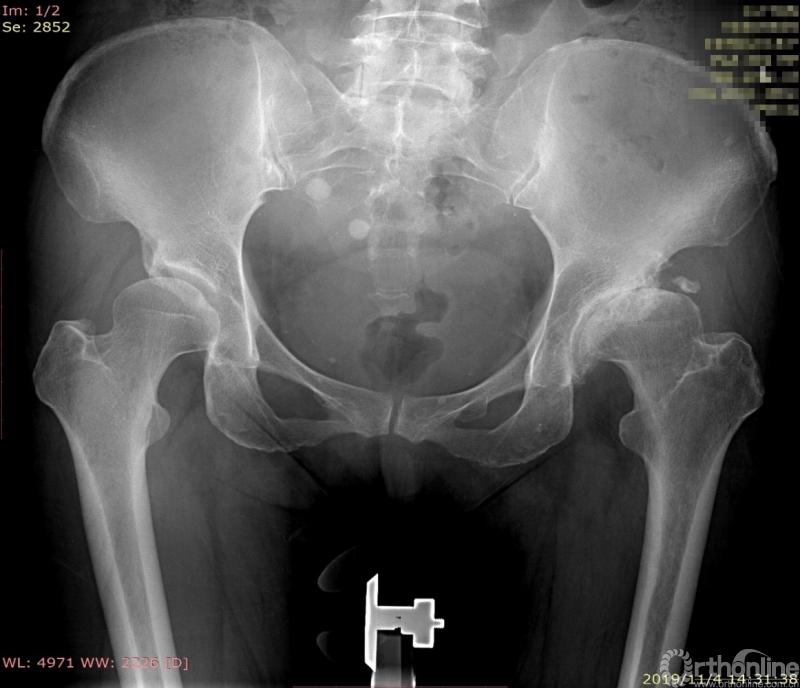

患者术前X线片,可见左侧患肢髓腔狭窄